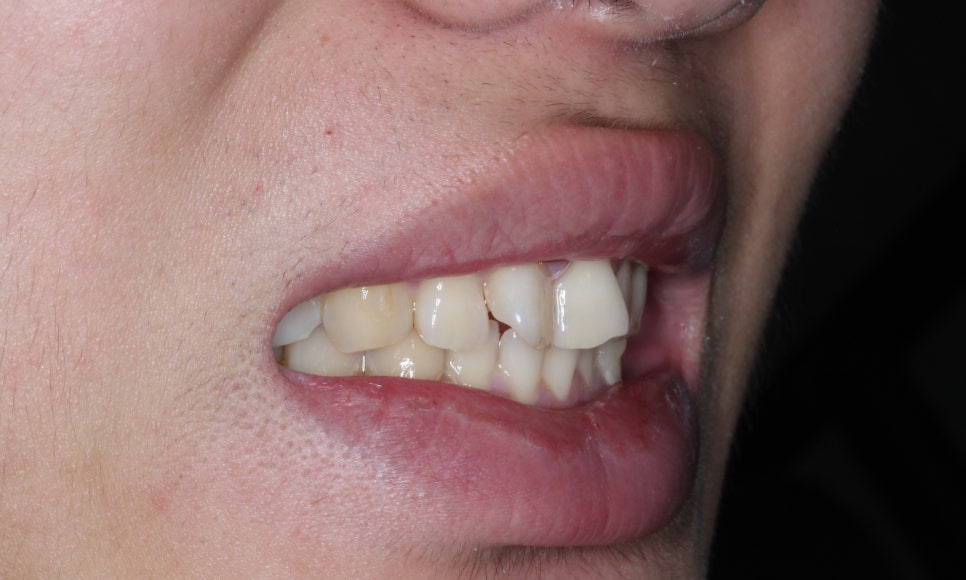

측면에서 보았을때 나비치아가

두드러져 보였던 교정 전과 달리

완만한 곡선의 형태로 앞니가 배열된

교정 후 모습입니다.